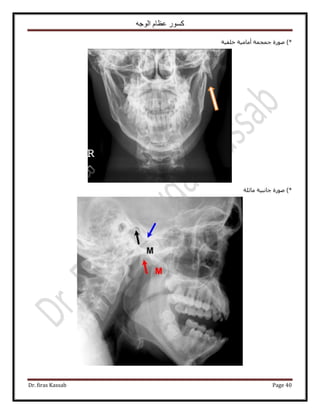

٢‫حُ٘ؼخػ‬ ٚ٤‫حُظ٘و‬:

‫ح٩ٗخٍس‬ ٖٓ ‫٫ري‬‫ح‬ ٞ‫ُزؼ‬‫كظخص‬ ٬ُٔ: ‫ٗؼخػ٤خ‬ ‫حُٞؿٜ٤ش‬ ‫ح٧ً٣خص‬ ٚ٤‫ط٘و‬ ٚ٤‫طٞؿ‬ ٝ ْٜ‫ُل‬

‫أ‬‫وال‬:

*٩‫ح‬ َ‫هز‬ ‫٣ـذ‬، ‫حُ٘ؼخػ٤ش‬ ‫حُٔلَىحص‬ ٠ِ‫ػ‬ ‫١٬ع‬‫أ‬٢٤‫ٗل‬ ٕ‫ػِٔخ‬٤‫حُظَ٘٣ل‬ ‫رخُٔ٘خ١ن‬ٝ ‫ٗؼخػ٤خ‬ ‫حُٔيٍٝٓش‬ ‫ش‬ٌَُٔ‫ح‬ ١ٞ‫روط‬‫أ‬ٝ

‫ٓ٘خ١ن‬‫حُولل٤ش‬ ‫حُٞؿٜ٤ش‬ ‫حُ٠ؼق‬.

*ُٔ‫ح‬ ٠‫حُطزو‬ َ٣ٜٞ‫حُظ‬ ‫ٗطزن‬ ‫هخٛش‬ ٚ‫حُٞؿ‬ ًٍٞٔ ٠َٟٓ ٢‫ك‬ٝ ٍٟٞ‫ل‬‫ٓلٍٞ٣ش‬ ‫ٓوخ١غ‬ ٖ‫ػ‬ ‫ػزخٍس‬ ٞٛ‫أ‬ٝ ‫١زو٤ش‬ ٝ‫ا‬‫ؿزٜ٤ش‬ ‫ًِ٤ِ٤ش‬

ٛٝ٢‫ر٤ٜ٘خ‬ َٜ‫٣ل‬ ‫حَُٝط٤٘٤ش‬ ‫حُٔوخ١غ‬3–5ٝ ْٓ‫ٍرٔخ‬‫أ‬ٝ ، َ‫ه‬٣٧‫ح‬ ُِٕٞ‫ح‬ ٍ‫ي‬ٝ ، ‫حُؼظ٤ٔش‬ ‫حُٔخىس‬ ٠ِ‫ػ‬ ٞ٤‫ر‬‫ح‬٧‫ح‬ ُِٕٞ٠ِ‫ػ‬ ‫ٓٞى‬

‫حُ٘لٔ٤ش‬ ‫حُٔخىس‬‫أ‬‫حَُهٞس‬ ‫حُ٘ٔؾ‬ ٝ.

‫ًؼخكخ‬ ‫٣َ٣٘خ‬ ‫ًٔخ‬ِٚ‫ريحه‬ ‫حُٜٞحء‬ ‫ٓغ‬ ٠ٌ‫حُل‬ ‫حُـ٤ذ‬ ‫ص‬‫أ‬‫ح‬ َ‫ريحه‬ ٝ‫ُلـخؽ‬‫أ‬ٍٞٓ‫ٗخ‬ ‫ٗظ٤ـش‬ ‫حُولق‬ ٌٖٝٝٔ٣‫ا‬‫حُٔوخ١غ‬ ٌٙٛ ٍ‫ٍٓخ‬‫ا‬٠ُ

ٝ ‫ُ٘خ‬ ‫ُ٤ـٜٔٔخ‬ َ‫حٌُٔز٤ٞط‬ٝ ‫ٓـٔٔخ‬ ‫ٓ٘ظَح‬ ‫٣ؼط٤٘خ‬ٝ ‫حُـَحكش‬ َ‫هز‬ ٚ‫حُٞؿ‬ َ‫ط٘خظ‬ ‫ُ٘خ‬ ْ٤‫٣و‬ ‫ٌٛح‬‫حُـَحك٤ش‬ ‫رؼي‬ ٚ‫ٟٝؼ‬ٝ‫أ‬ٟ‫ٓٔخإ‬ ْٛ

ُ‫ح‬ ‫ٌٛح‬٧‫ح‬ ٠‫حُؼ٬ػ‬ ٍٟٞ‫حُٔل‬ ٠‫حُطزو‬ َ٣ٜٞ‫ظ‬‫رؼ‬‫ٌُٔ٤ش‬ ٞ٣َُٔ‫ح‬ َٝ‫طؼ‬ ٢ٛ ْٔ‫حُٔـ‬ ‫خى‬‫أ‬‫ح٫ٗؼش‬ ٖٓ َ‫ًز‬.

‫ثاٍّا‬:

*٠ٔ٤١‫حُٔـ٘خ‬ ٖ٤َُٗ‫ح‬ٍُٚٝ‫ى‬‫أ‬ٝ ‫حُِٔٓ٘ش‬ َُٟٝٞ‫ح‬ ٢‫ك‬ َ‫ًز‬‫حُلخىس‬ ‫ُ٤ٔض‬.

ٝ٧‫ح‬ ٚ٤‫ك‬ ‫٣ظ٠ق‬ٌَ٘‫ر‬ ‫حُـ٠َٝك٤ش‬ ّ‫هٔخ‬‫أ‬ٖٓ َ‫ًز‬CTٝ٠ٌ‫حُل‬ َٜ‫حُٔل‬ ٢‫ك‬ َٙ‫حُو‬ ‫هخٛش‬.

*ٕ‫حَُٔٗخ‬ َ٠‫٣ل‬٠ِ‫ػ‬C Tٝ ، ‫حُؼ٠٬ص‬ ٙٞ٘‫ط‬ ‫ٓؼَكش‬ ٢‫ك‬ٝ ‫حُلـخؽ‬ َ‫ىحه‬ ‫حُِ٘ف‬ ‫طلي٣ي‬ٝ ‫حُٔٔلخم‬ ‫طلض‬٩‫ح‬ٝ ‫ٜٗزخرخص‬‫طلي٣ي‬

٧‫ح‬٧‫ح‬ ّ‫ؿٔخ‬‫حُٔؼيٗ٤ش‬ َ٤‫ؿ‬ ‫ؿ٘ز٤ش‬‫أ‬ًٔ ‫طلي٣يٛخ‬ ْ‫ك٤ظ‬ ‫حُٔؼيٗ٤ش‬ ‫ٓخ‬‫خ‬٢‫ك‬C T

*َ٠‫٣ل‬MRI٢‫ك‬‫أ‬‫ػخٓش‬ ٕ‫حُِٔخ‬ ٝ‫َٓح‬ٝ٧‫ح‬ّ‫ٍٝح‬ُٝ‫ح‬‫ظ٘ٞٛخص‬.